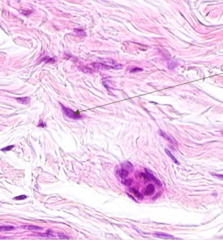

fibroblast

Front

what is the name of this cell?

Back